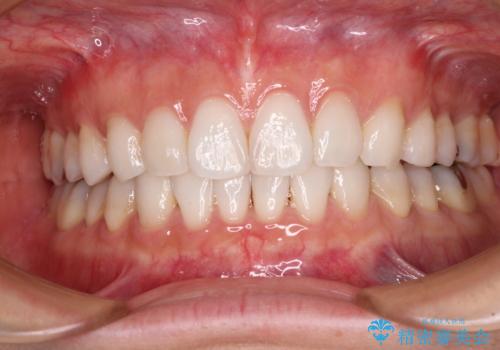

- 前歯のデコボコを気にして来院された患者様です。

海外に留学をされており、卒業後はしばらく日本にいるものの、再び就職のため出国するとのことでした。

定期的に日本に戻ってくる予定であるため、来院頻度の少ないインビザラインにて矯正治療を行うこととしました。

歯列不正が軽度であり、インビザラインの装着時間を遵守してくださったため、日本と海外を行き来しながらも2年弱でしっかりと仕上げることができました。